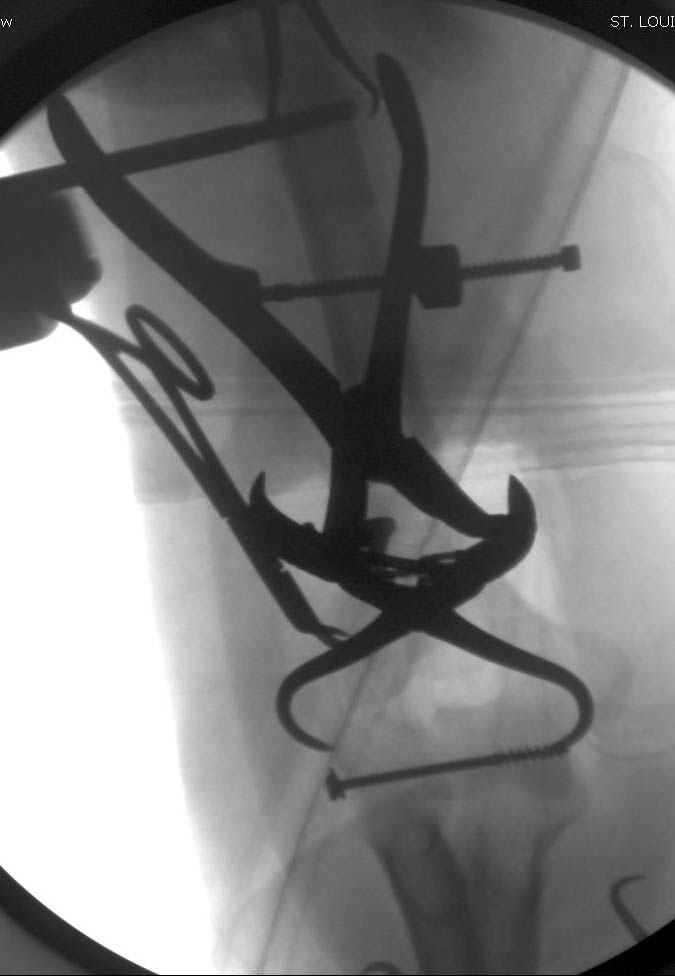

Djoldas Kuldjanov, M.D. 09 Сентябрь 2005, 20:07

Примерный случай, только перелом был открытый, в задне-медиальной стороне рана около 2 см по характеру "изнутри кнаружи", неврологический статус со слабостью сгибания мизинца, также слабая абдукция и аддукция указательного пальца и сгибания в кисти.

Больному сделали обработку и наложили временный аппарат внешной фиксации плечо-предплечье.

На шестой день сделали открытую репозицию чрезлоктевым доступом двумя locking plate, локтевой нерв был ушибленным, после операции положительная динамика в Flexor Carpi Ulnaris. Фиксацию локтевого отростка произвели tension band technique с дополнительным шурупом.

Этапы операции на снимках....

Джолдас Кульджанов

Djoldas Kuldjanov, MD

Department of Orthopedic Surgery

St. Louis University Medical Center